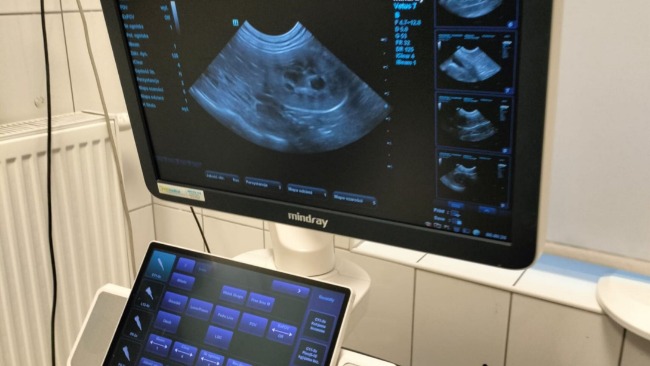

Biorąc pod uwagę bardzo zły obraz obu nerek w badaniu USG (całkowicie zwłókniałe) podwyższony mocznik jest złą wiadomością i może wskazywać na początek niewydolności nerek, która niestety nie jest uleczalna.